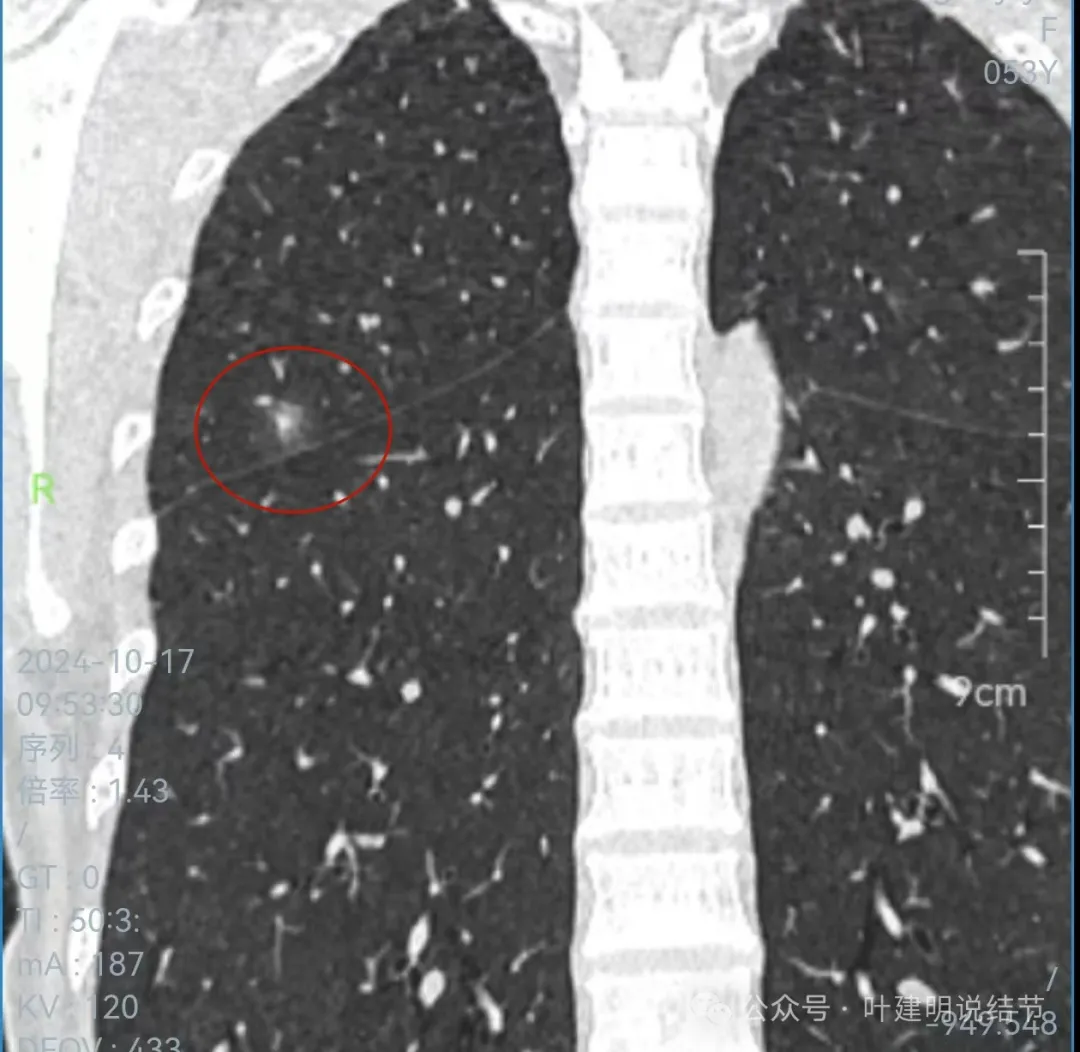

冠状位上看病灶有实性成分,实性成分缺乏收缩力,外围是淡磨玻璃成分,瘤肺边界欠清,贴着叶裂没有影响。

从连续层面以及影像细节上看,这个病灶就不可能是恶性的!短期内出现,混合密度而瘤肺边界不清,整体缺乏收缩力也无膨胀性,灶内实性成分不致密且磨玻璃成分过淡,灶内血管有异常增粗与密度过高,又是两肺多发病灶。这所有的表现与病情发展都与感染性病变契合,周围淡磨就是炎症水肿的关系,血管异常就是管壁有炎症的关系,多发就是感染(致病因素)影响两肺的关系。怎么可能是恶性?

肺结节看影像考虑良性还是恶性,从细节上分析影像特征当然是很重要的,但在炎性恢复期有时表现的与肿瘤性质的几乎没有区别,我们自己也在这上面吃过亏,明显混合磨玻璃结节约2厘米,没有随访直接切除后是肺泡上皮增生的,回想或许若术前复查一次,病灶大概明显吸收好转了的。今天分享的这个病例,我认为不可能是恶性的,包括4B这处。原因如下:1、间隔20天,从无到有,并表现为混合磨玻璃密度,若是肿瘤性质没有这么快,不符合磨玻璃肺癌的生物学行为的;2、多发病灶短期内出现,更用炎症能够解释,而用肿瘤不能解释;3、所谓主病灶考虑4B的,整体轮廓虽较清,但瘤肺边界偏模糊,磨玻璃成分密度过低而中间实性成分密度较高,却又缺乏收缩力。病灶紧贴叶间裂,但没有任何牵拉,无胸膜凹陷。其实以上这几点就是炎症性的最重要依据。看肺结节,判断良恶性,不能只纠结于影像表现,要有综合观、全局观,要考虑临床上是否解释得通。